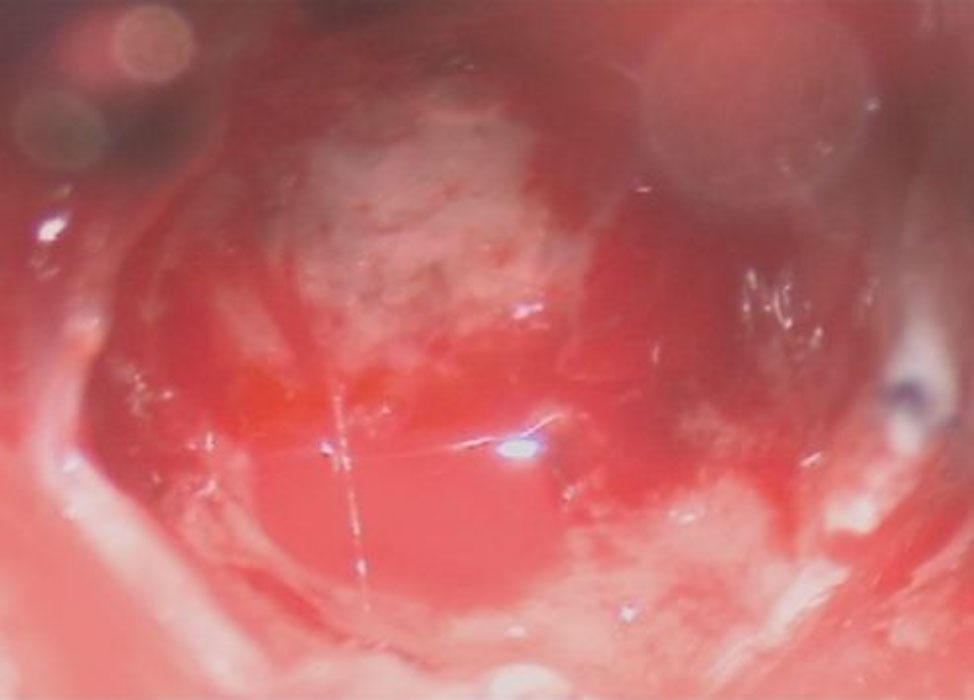

摘出 後